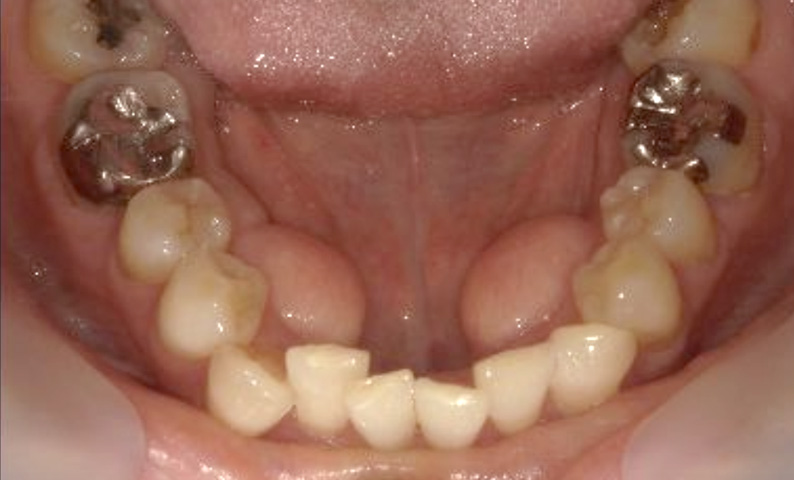

症例_003 下顎だけの部分矯正

治療期間:10ヶ月金額:24万円+税女性前歯のガタガタ下の前歯だけ上顎は補綴治療中

| Before | After |